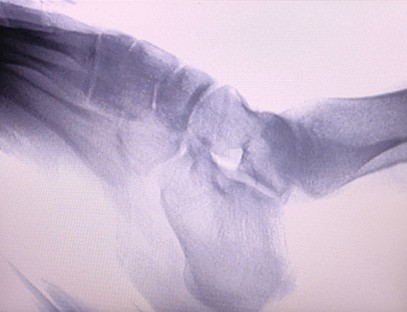

Il-Magni Ortopediċi tar-Raġġi X tagħna huwa prodott ta 'kwalità għolja li kien iddisinjat partikolarment għall-immaġini ortopediċi. Jista 'jintuża għad-dijanjosi u l-ippjanar tat-trattament ta' kundizzjonijiet ortopediċi varji, inklużi ksur, dislokazzjonijiet, artrite u tumuri fl-għadam. Hija mgħammra b'teknoloġija avvanzata tar-raġġi-X li tippermetti immaġini ta 'kwalità għolja b'espożizzjoni mnaqqsa għar-radjazzjoni. Il-magna għandha sistema ta 'immaġni b'riżoluzzjoni għolja u tista' taqbad immaġini ta 'kwalunkwe struttura tal-għadam b'ċarezza kbira.

Il-Magna Ortopedika tar-Raġġi X tagħna tista 'tintuża f'diversi speċjalitajiet mediċi, inklużi l-ortopedija, newroloġija, u mediċina ta' emerġenza. Ħafna drabi jintuża għall-osservazzjoni fluworoskopika ta 'għadam tar-riġlejn umani, Sptarijiet veterinarji u domestiċi, Trattament ta' feruti f'siti sportivi, bini, vapuri tal-oċean, żoni remoti u siti tal-kamp militari. Uħud mill-applikazzjonijiet kliniċi jinkludu:

1. Dijanjosi ta 'ksur, dislokazzjonijiet, u korrimenti oħra fl-għadam.

2. Evalwazzjoni ta 'mard tal-ġogi bħal artrite, mard tal-ġogi deġenerattiv, u osteoporożi.

4. Ippjanar ta 'qabel l-operazzjoni għal kirurġiji ortopediċi.